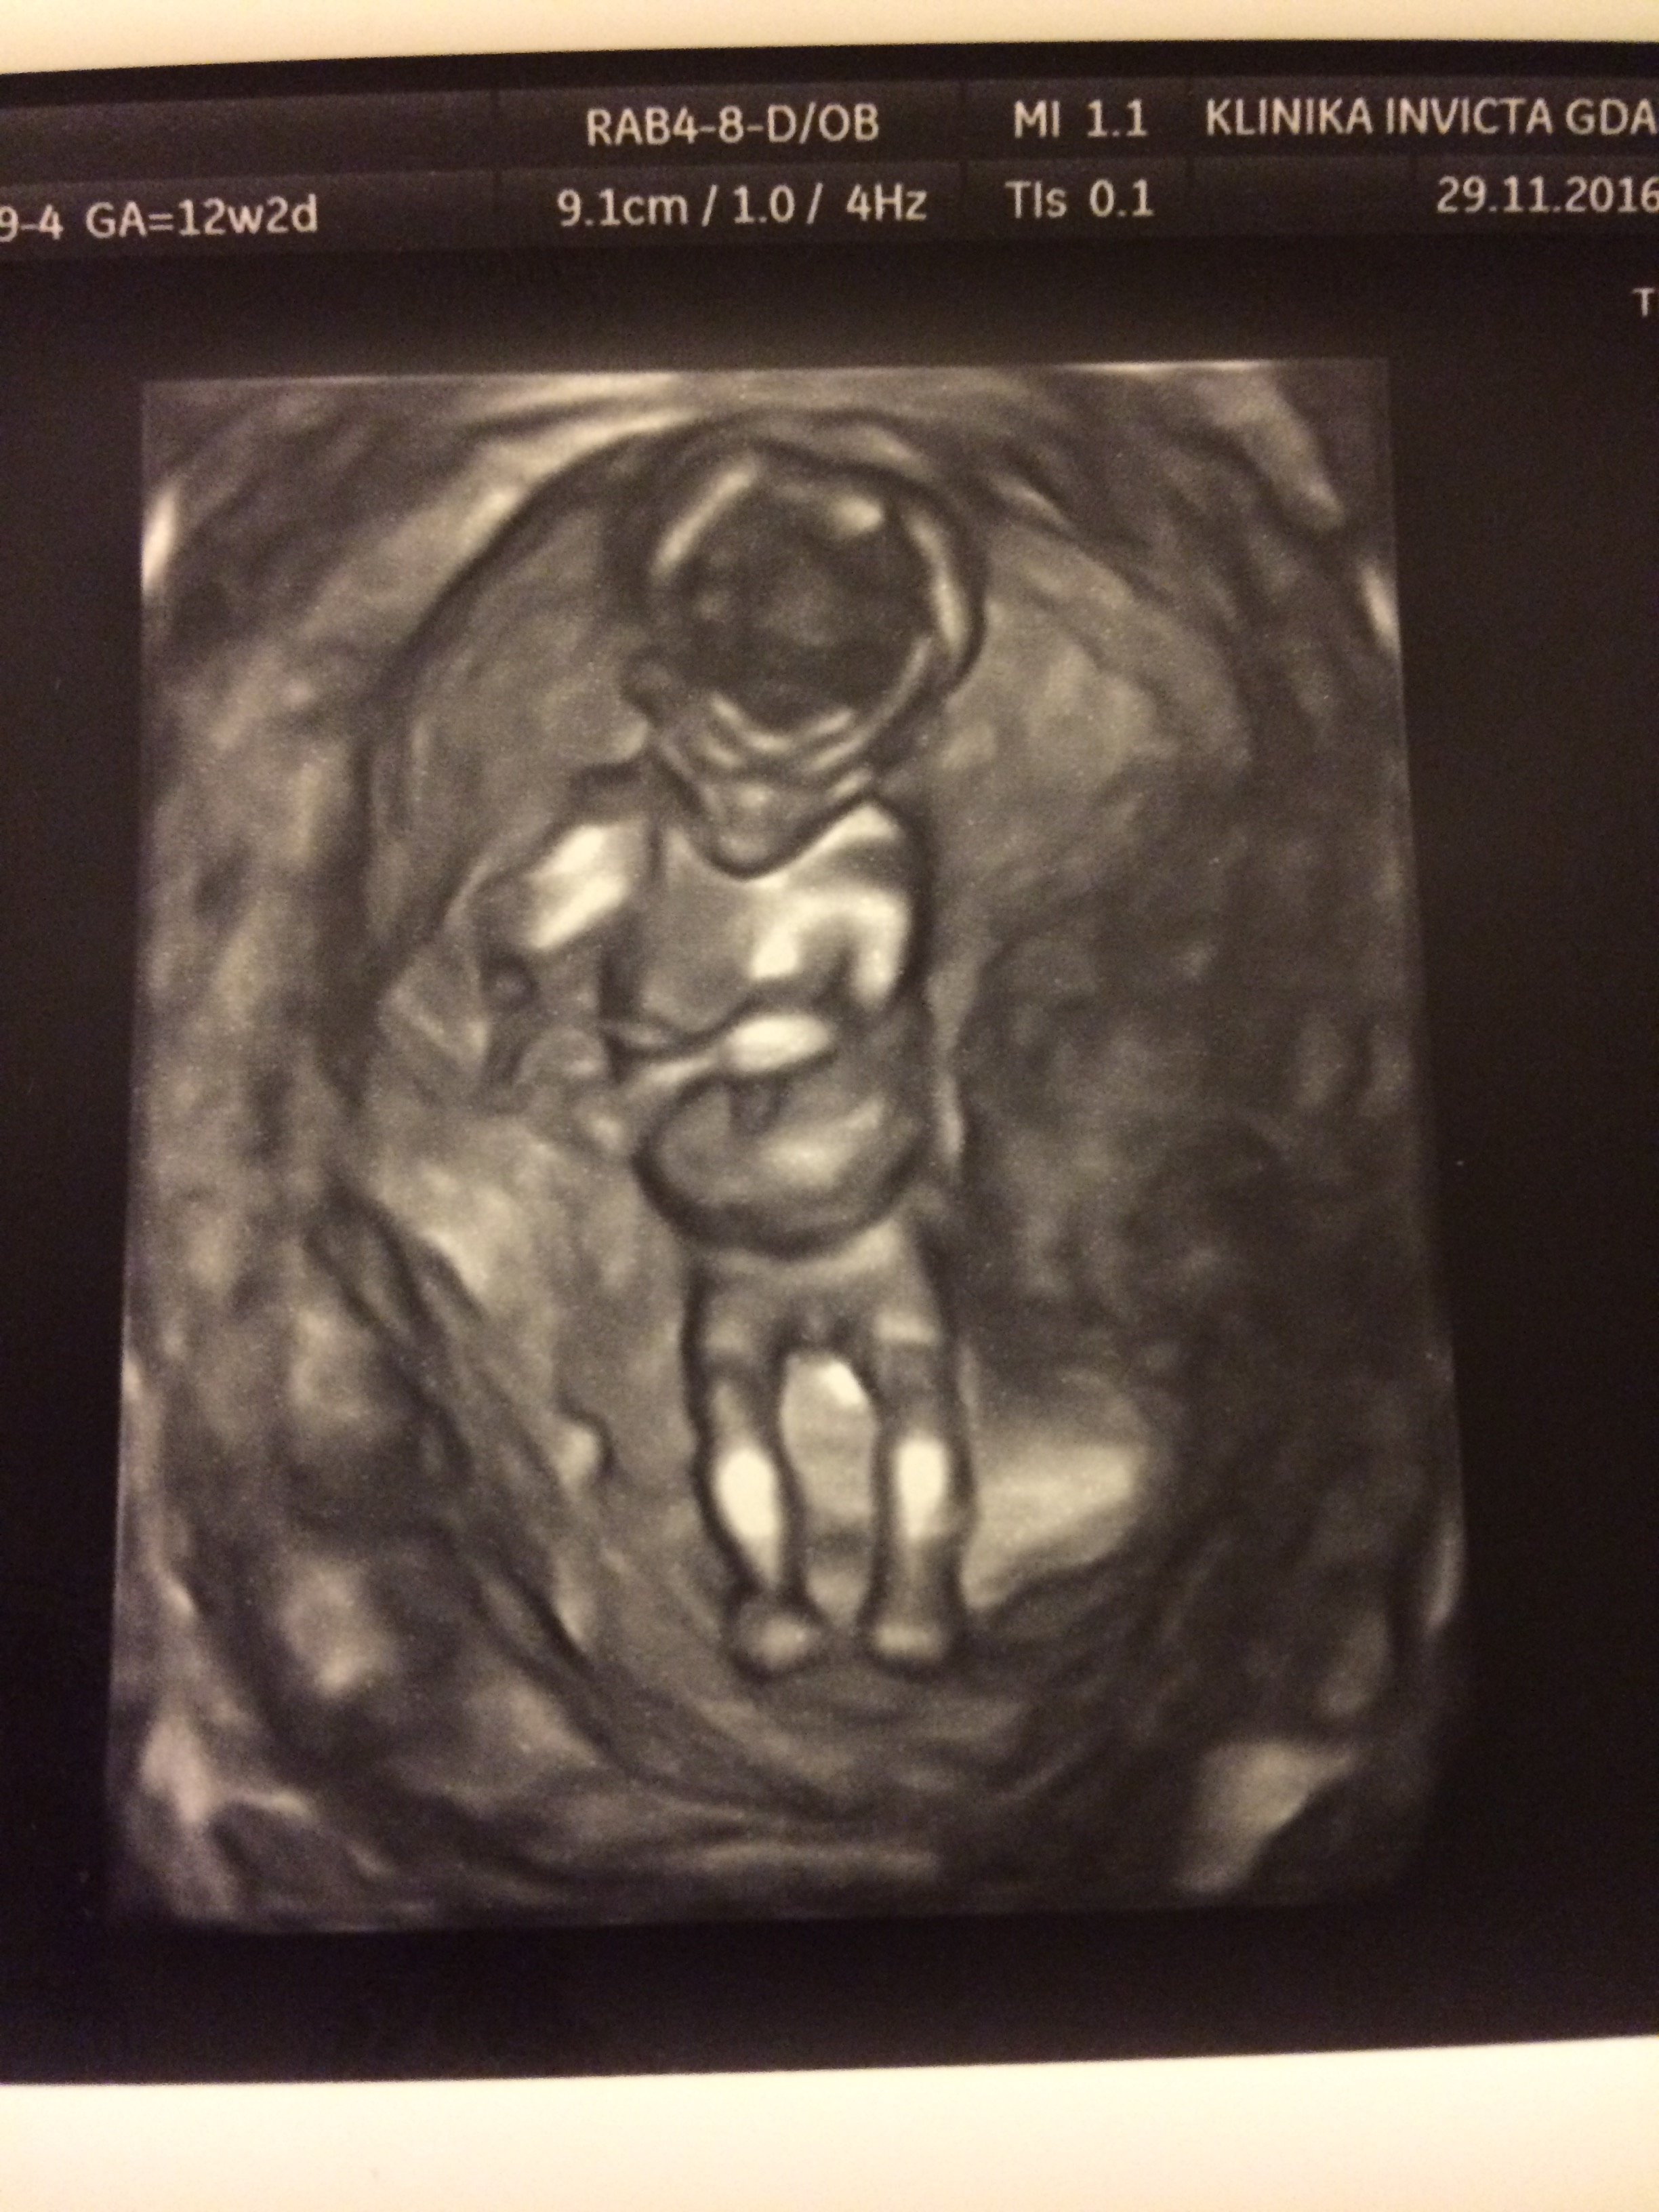

Dziś miałam z mężem dzień wolnego, bo nie tylko musieliśmy ogarnąć prezenty na Święta (nie robimy takich rzeczy na ostatnią chwilę by oszędzić sobie stresu), ale jechaliśmy do Gda na USG 1.trymestru! Prawdę mówiąc pomieszane były emocje ekscytacji z obawami, które chyba każda gdzieś tam ma. Niewiele rosnę, póki co poza mdłościami niewiele czuję... ale ciagle towarzyszy mi uczucie że jest tam ten mój Mały Ktoś

Nie zanudzając... obawy okazały się zbędne, a nasz Maluszek ma się cało i zdrowoPodczas badania uraczył nas ruszającym się nóżkami i rączkami. Magiczne uczucie

Całe 6,1cm Człowieka.